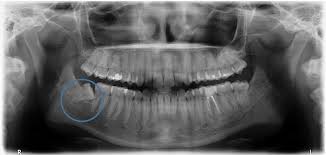

Von der Wuchsrichtung des Zahnes davon wie viel von dem jeweiligen Zahn bereits im Kiefer angelegt und verwachsen war und. Verläuft der Durchbruch der Weisheitszähne bei einigen Menschen ohne Komplikationen so leiden andere unter starken Schmerzen und Entzündungen die sich über mehrere Monate hinweg ziehen. Schmerzen nach dem Ziehen der Weisheitszähne.

Wie stark die Schmerzen sind und wie lange sie andauern hängt von einigen Faktoren ab. Dann allerdings sollten diese langsam abklingen. Bei den meisten Entfernungen der Weisheitszähne entstehen nur leichte Schmerzen oft hat man überhaupt keine.

Es dauert je nach der Größe des Weisheitszahns und sonstigen Faktoren recht lange bis die Wunde vollständig verheilt ist. Das durchschnittliche Alter in dem die Weisheitszähne durchbrechen beträgt etwa 16 Jahre. Es kann 7-14 Tage dauern bis sie vollständig abklingen.

Dann allerdings sollten diese langsam abklingen. Ist das nicht der Fall und verstärken sich die Schmerzen sogar sollte dringend der Zahnarzt aufgesucht werden. Ablauf Ablauf was Sie beachten müssen. Schmerzen nach Weisheitszahn OP wie lange normal. Wie lange dauern die Schmerzen normalerweise an. Es kann 7-14 Tage dauern bis sie vollständig abklingen. Die Fäden zieht der Zahnarzt in der Regel nach 7-10 Tagen. Mit welchem Alter brechen die Weisheitszähne durch. Die Schmerzen nach einer Weisheitszahn OP können 7 bis 14 Tage anhalten allerdings mit abklingender Intensität.

Dies hängt natürlich hauptsächlich von der Schwere des Eingriffs ab. Die Schmerzen können jedoch schon unmittelbar nach einigen Stunden nach dem Eingriff abklingen. Auch am nächsten Tag muss meist noch mit Schmerzen gerechnet werden. Wie lange dauern die Schmerzen nach einer Weisheitszahn-OP. Nach der Entfernung der Weisheitszähne sind die Wangen und der Mundbereich bei den meisten Patienten geschwollen. Verläuft der Durchbruch der Weisheitszähne bei einigen Menschen ohne Komplikationen so leiden andere unter starken Schmerzen und Entzündungen die sich über mehrere Monate hinweg ziehen. Dies hängt natürlich hauptsächlich von der Schwere des Eingriffs ab.